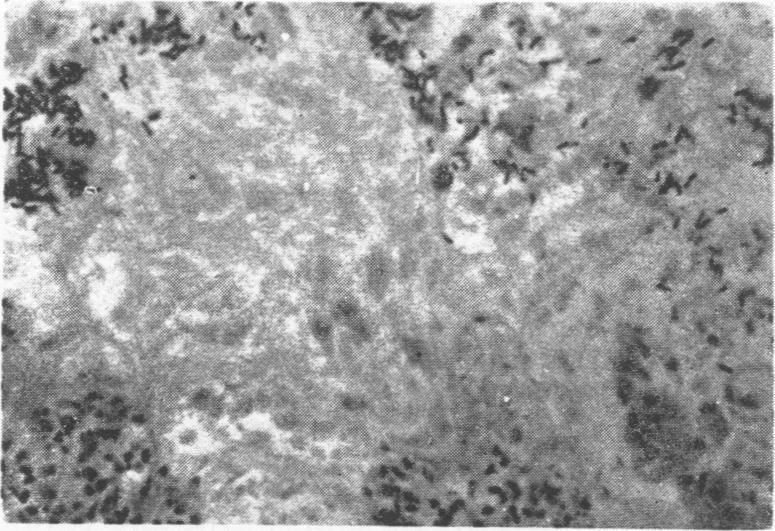

Necrotic enteritis was reproduced experimentally in two week old broiler chickens by intravenous injection and also by oral administration of a pure culture of Clostridium perfringens. In the first experiment, gross and microscopic intestinal lesions, typical of necrotic enteritis, were observed in all diseased birds and mortality was obtained only in the group of birds that were injected with 0.4 ml or more of the pure culture of the microorganism. In the second experiment, the highest mortality was noted in the group of birds that received orally, in addition to the Clostridium culture, a solution of sodium bicarbonate, to obtain an alkaline intestinal content and opium to decrease the intestinal peristaltism. The gross and microscopie intestinal lesions of the diseased and killed birds were more severe than those observed in the other groups and were similar to those encountered in field outbreaks of necrotic enteritis.

通过静脉注射以及口服产气荚膜梭菌纯培养物,在两周龄的肉鸡中进行了坏死性肠炎的实验性复制。在第一个实验中,在所有患病禽类中均观察到了典型的坏死性肠炎的大体和微观肠道病变,并且仅在注射了0.4毫升或更多该微生物纯培养物的禽类组中出现了死亡情况。在第二个实验中,除了梭菌培养物外,口服碳酸氢钠溶液以获得碱性肠道内容物并口服鸦片以降低肠道蠕动的禽类组中死亡率最高。患病和扑杀禽类的大体和微观肠道病变比其他组中观察到的更为严重,并且与坏死性肠炎田间暴发中遇到的病变相似。